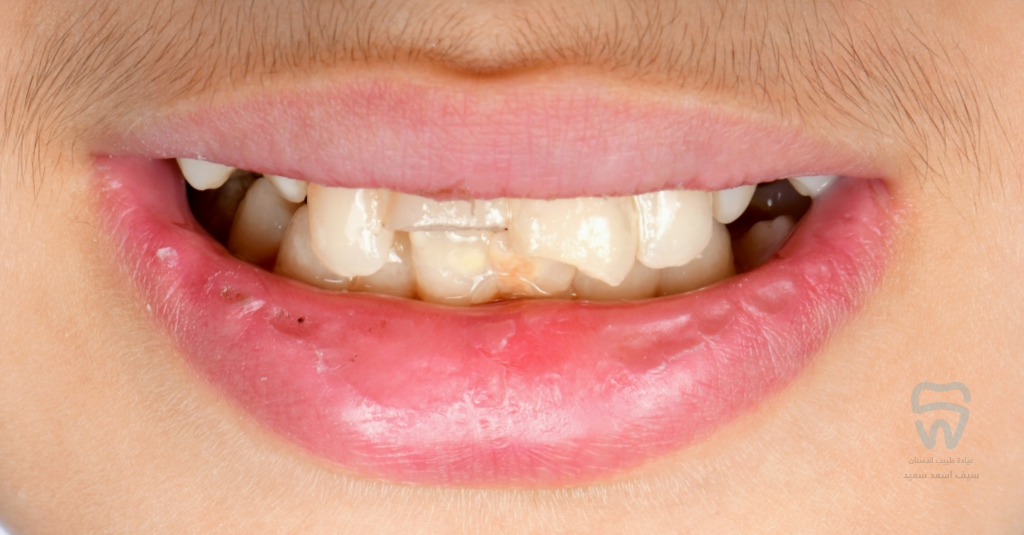

patient came with 2 fractured upper centrals

closer look at the condition